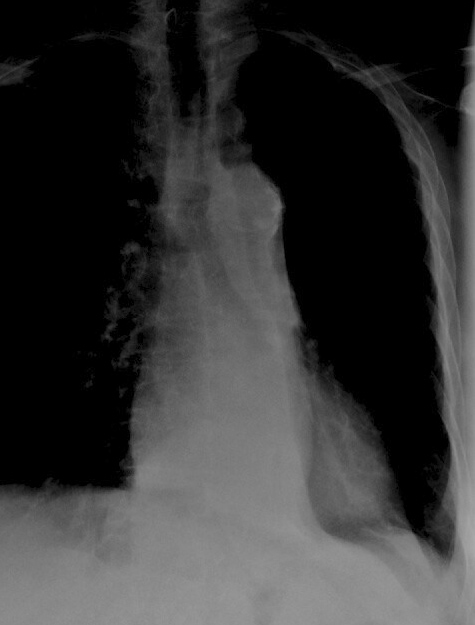

LLL Collapse Case 7 PA